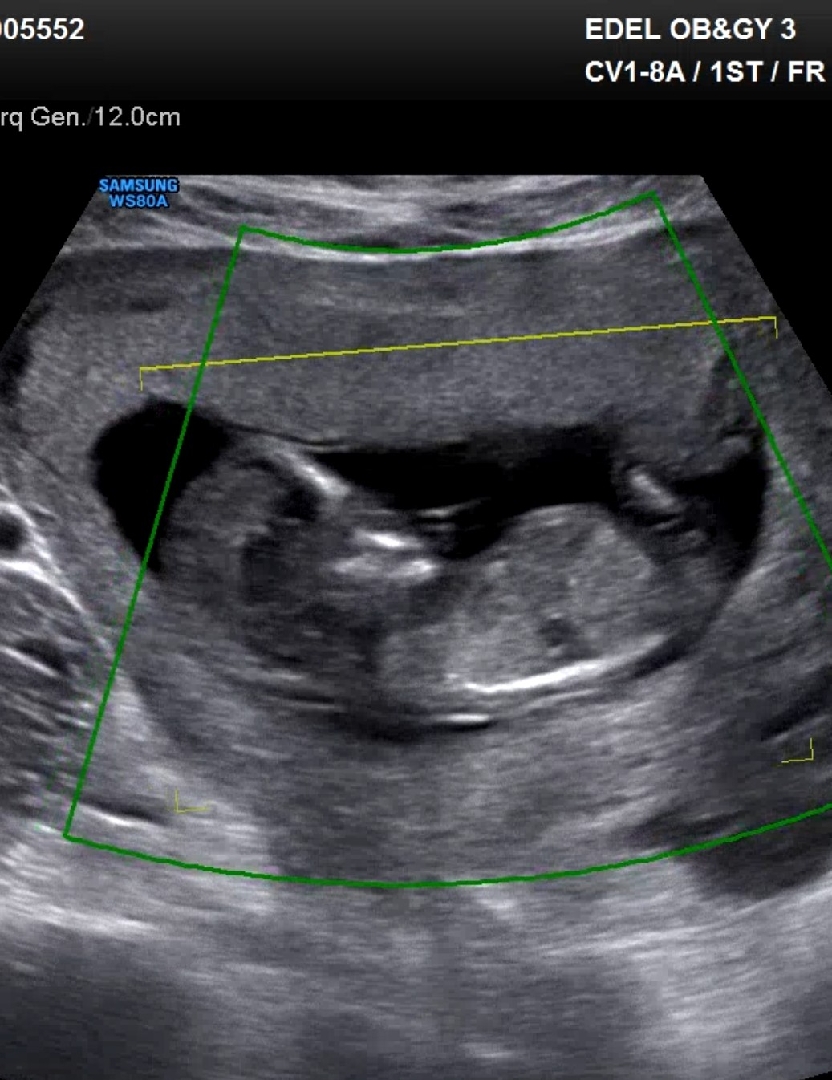

12주 각도 한번 봐주세여!

제가 봤을 땐 평행한데 ㅠㅡㅠ 자꾸 봐서 그런가 싶어요 ㅠㅠ 아들각도 일까요?